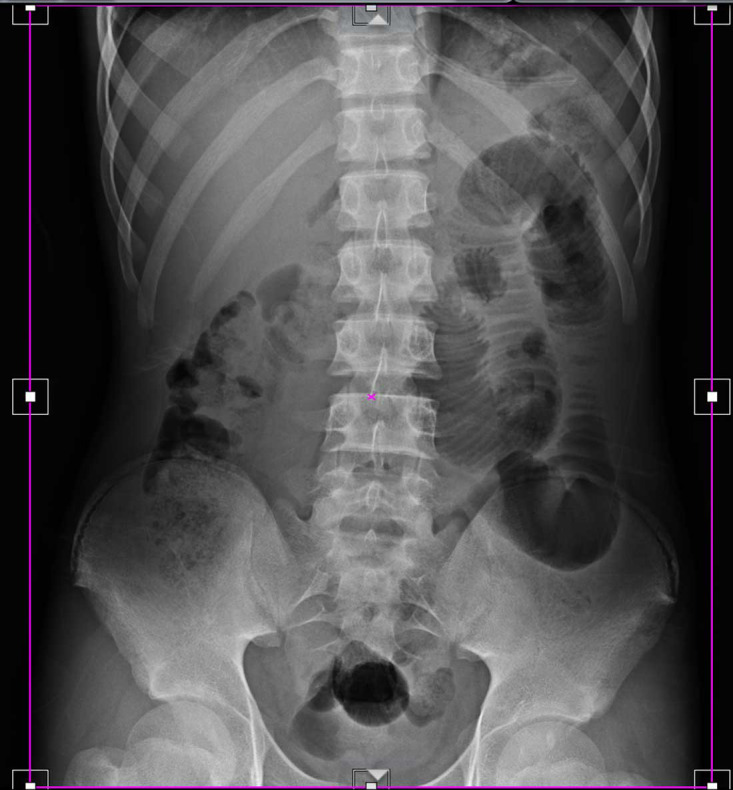

Material and methods: This retrospective analysis was conducted on digital X-ray machine images. Quality control tests were performed to ensure equipment accuracy, and image cropping was then measured by analyzing archived images. Finally, the cropped image fraction and associated unnecessary radiation doses were calculated.

Results: Quality control tests confirmed that all imaging equipment was functioned within acceptable alignment and angle tolerances. The analysis of 911 images revealed a high prevalence of cropping (82%), with significant variation across different projections. Lateral knee images exhibited the highest cropping rate (96.2%), while abdominal images had the lowest (36.1%).